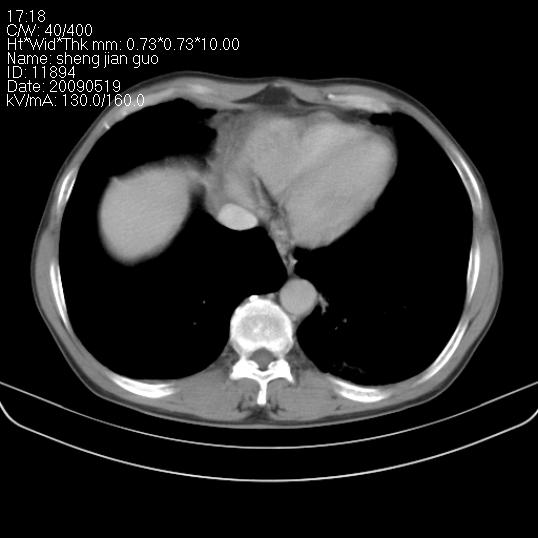

以下是引用zjzjr在2009-5-19 17:25:00的发言:[br]支持楼主考虑,另左肺下叶阻塞性炎症。

以下是引用zhao_bin2008在2009-5-19 17:48:00的发言:[br]支持左肺下叶周围型肺癌并阻塞性肺炎。

以下是引用zsl6918在2009-5-20 7:10:00的发言:[br]左侧中心型肺癌!